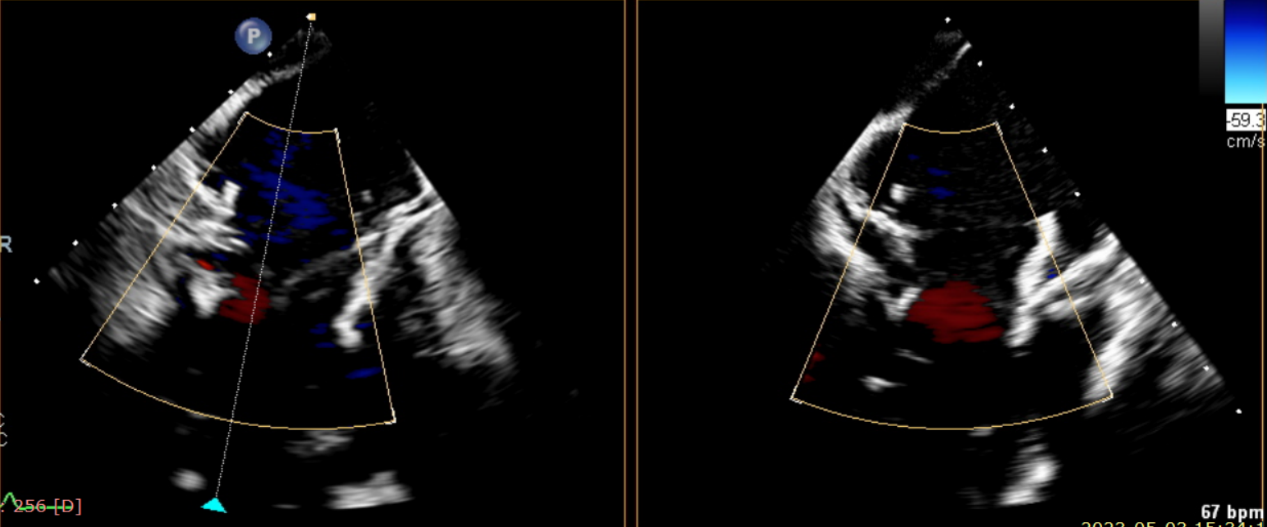

第一名患者是一位86歲的女性,既往有高血壓、高脂血癥、糖尿病、短暫性腦缺血發(fā)作(TIA)、左側(cè)頸動脈瘤、射血分?jǐn)?shù)保留的慢性心力衰竭、持續(xù)性房顫、甲狀旁腺切除術(shù)后原發(fā)性甲狀旁腺功能亢進(jìn)的病史。曾于2022年7月因急性失代償性心力衰竭和容量超負(fù)荷入院。本次入院是由于心力衰竭和嚴(yán)重的三尖瓣關(guān)閉不全導(dǎo)致的呼吸困難、胸痛、腹脹和雙下肢水腫加重。

第二名患者是一位72歲的女性,既往有心力衰竭、冠狀動脈疾病、高血壓、高脂血癥、糖尿病、陣發(fā)性房顫的病史。她曾多次由于呼吸急促和下肢水腫到醫(yī)院就診。本次入院的原因是由于加重的心衰和三尖瓣關(guān)閉不全所導(dǎo)致的呼吸急促。